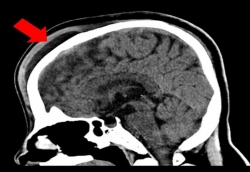

경희의료원 협력병원인 참조은병원 신경외과 의료진이 난치성 두피하혈종(Subgaleal Hematoma, SGH) 치료의 새로운 방향을 제시해 학계 주목을 받고 있다.난치성 두피하혈종은 외상으로 두피 아래 공간에 혈액이 고이는 질환으로 성인에게는 매우 드물게 발생한다.기존 압박 드레싱이나 바늘흡인 등 보존적 방법으로 치료돼 왔지만 '정맥 지속 출혈', '혈액 침윤', '자발적 지혈 불가' 등의 특성으로 재발이 빈번했다.치료 사례인 37세 여성환자는 외상 후 두피하혈종이 발생해 참조은병원을 찾았고, CT 검사에서 전두골 골절을 확인…